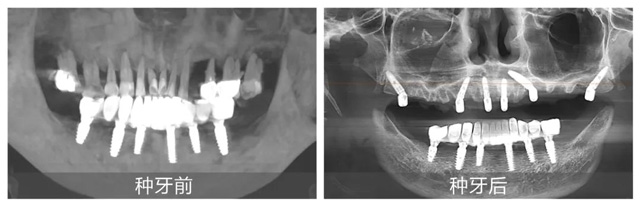

在配備數字化導板系統的現代化手術室里,黃杰終于迎來期盼已久的“試煉場”。短短一年,就已經成功種植修復2100+顆牙,完成無牙頜即刻負重手術110臺。不僅在種牙數量上取得了突破,在質量方面也同樣出色。